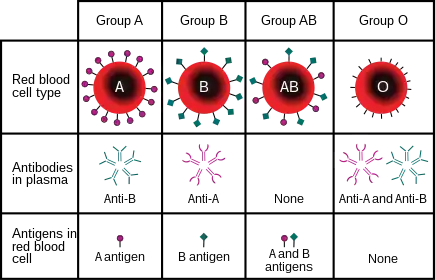

The ABO blood group system is used to denote the presence of one, both, or neither of the A and B antigens on erythrocytes.[1] For human blood transfusions, it is the most important of the 44 different blood type (or group) classification systems currently recognized by the International Society of Blood Transfusions (ISBT) as of December 2022.[2][3] A mismatch (very rare in modern medicine) in this, or any other serotype, can cause a potentially fatal adverse reaction after a transfusion, or an unwanted immune response to an organ transplant.[4] The associated anti-A and anti-B antibodies are usually IgM antibodies, produced in the first years of life by sensitization to environmental substances such as food, bacteria, and viruses.

Thus, he discovered two antigens (agglutinogens A and B) and two antibodies (agglutinins – anti-A and anti-B). His third group (C) indicated absence of both A and B antigens, but contains anti-A and anti-B.[10] The following year, his students Adriano Sturli and Alfred von Decastello discovered the fourth type (but not naming it, and simply referred to it as "no particular type").[11][12]